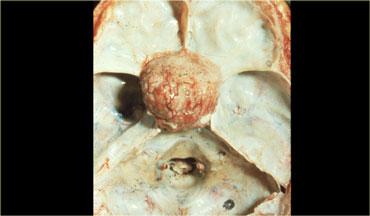

U màng não (Meningioma)

U màng não (meningioma) là khối u nội sọ thường gặp nhất ở người lớn, với 20% trường hợp xuất hiện tại nền sọ.

Đây là mẫu bệnh phẩm tử thiết sau khi đã lấy não ra, cho thấy một u màng não nằm trên màng hoành yên (diaphragma sellae).

U màng não hầu như luôn là tổn thương đặc, đôi khi có nang ở rìa.

Khối u có thể đẩy nhẹ màng nhện lên và thường ngấm thuốc đồng nhất.